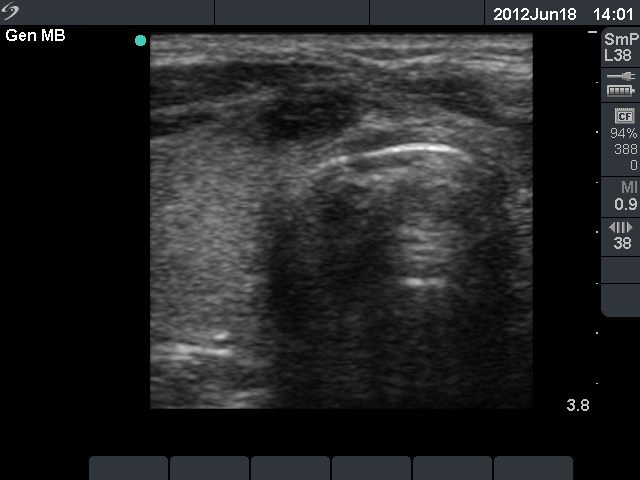

First row: ultrasonographic picture before sclerotherapy. The size of the lesion was 38x28x39 mm (width x depth x length).